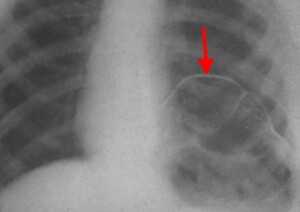

Нейрогенные парезы дыхательной мускулатуры осложняют течение ряда заболеваний центральной и периферической нервной системы. В отдельных случаях они могут быть преобладающими или единственно манифестными, вызывая диагностические трудности имитацией заболеваний дыхательной системы. Парезы диафрагмы и развившаяся на этом фоне дыхательная недостаточность могут быть следствием множества патологических процессов, включая миелит, болезни мотонейрона, полинейропатии, болезни нервно-мышечных синапсов, некоторые миопатии, герпетические полирадикулоневриты, травматические повреждения диафрагмального нерва, поражения шейного сплетения, заболевания грудной клетки и поддиафрагмальные патологические процессы [17]. Причины дисфункции диафрагмы можно классифицировать в зависимости от уровня поражения [4]. Продолговатый или спинной мозг поражается при демиелинизирующем процессе, однако парез диафрагмы довольно редко встречается при рассеянном склерозе [12, 18]. Высокое поражение спинного мозга (на уровне С1 или С2) приводит к параличу диафрагмы, в то время как при среднешейном поражении (на уровне С3-С5) функция диафрагмы частично сохраняется. Около 40% пациентов с поражением на уровне С3 нуждаются в искусственной вентиляции легких (ИВЛ), и лишь 15% пациентов с повреждением на уровне С4 или С5 [18, 33]. Заболевания верхних мотонейронов спинного мозга, как, например, боковой амиотрофический склероз или полиомиелит, часто приводят к дисфункции диафрагмы и дыхательной недостаточности. Парез диафрагмы может развиться как непосредственно сразу после инфицирования вирусом полиомиелита, так и спустя многие годы (в среднем, 35 лет) [9, 18]. К другим причинам, вызывающим парез диафрагмы и захватывающим мотонейроны спинного мозга относятся сирингомиелия, паранео-пластические моторные нейропатии и спиналь-ные мышечные атрофии. В большинстве случаев причиной осложнений и летального исхода при этих состояниях является дыхательная недостаточность [18]. Повреждение непосредственно самого диафрагмального нерва - чаще всего результат ятрогенного воздействия на него во время операции или сдавления опухолью [18, 21, 28]. В литературе описаны случаи проявления аневризмы грудного отдела аорты в форме паралича диафрагмального нерва. Симптомы также включали дисфонию, хроническую боль в груди и прогрессирующую дисфагию [5, 24]. К другим состояниям, способным вызвать непосредственное поражение диафрагмального нерва можно отнести травмы, инфекционные поражения (герпетическая инфекция, болезнь Лайма) и воспалительные процессы. Синдром Гийена-Барре часто осложняется вовлечением диафрагмального нерва [18, 31]. Так, от 20% до 30% госпитализированных пациентов с установленным диагнозом синдрома Гийена-Барре нуждаются в эндотрахеальной искусственной вентиляции легких [15]. Согласно данным исследования в Англии 25% и 23% [15] больным синдромом Гийена-Барре необходима ИВЛ [6]. Известно, что приблизительно у 5% пациентов с невралгической амиотрофией (синдромом Пэрсонейдж-Тёрнера) имеется вовлечение диафрагмального нерва [18, 29]. Болезни с нарушением синаптической передачи могут манифестировать с дисфункции диафрагмы. Острая дыхательная недостаточность часто возникает при миастеническом кризе, что приводит к необходимости искусственной вентиляции легких. Реже дисфункция диафрагмы встречается при синдроме Ламберта-Итона, ботулизме, наследственных и приобретенных миопатиях, а также при отравлении аминогликозидами, фосфорорганическими веществами [18]. Важно помнить о вероятности развития атрофии диафрагмы, которая может возникнуть даже после короткого периода искусственной вентиляции легких. Она связана с атрофией как быстро, так и медленно сокращающихся мышечных волокон. Так, недостаточное питание или такие метаболические сдвиги, как гипофосфатемия, гипомагниемия, гипокалиемия, гипокальциемия могут способствовать дисфункции диафрагмы и продлевать потребность в искусственной вентиляции [14, 18, 19]. Среди пациентов с диспноэ, ортопноэ или гиперкапнической дыхательной недостаточностью неуточненной этиологии следует учитывать возможность наличия нейропатии диафрагмального нерва (НДН) [30]. В современной литературе она часто описывается в сочетании с болью в шее и плече, часто возникающей после инфекционных заболеваний или операций, что позволило считать НДН возможной состовляющей невралгической амиотрофии плечевого пояса (синдрома Персонейджа-Тернера). Идиопатическая НДН, вероятно, является отдельной нозологической формой в спектре иммуноопосредованных фокальных нейропатий, и, напротив, не ассоциирована с такими симптомами как боли в плече, шее, парезом верхней конечности [16, 17, 20, 23, 29, 30, 32]. Различают одностороннюю и двустороннюю НДН. Односторонняя НДН зачастую не приводит к значимым дыхательным нарушениям и протекает клинически бессимптомно, что объясняет ее гиподиагностику и, как следствие, малую распространенность описаний в литературе [16, 23]. Интерес представляет клиническое наблюдение НДН, сделанное в нашей клинике. Больной К., 39 лет, поступил в приемное отделение Республиканской клинической больницы 09.04.2015 г. с жалобами на выраженную одышку экспираторного характера в покое, сухой непродуктивный кашель, повышение температуры до 37,6˚С. Заболел около 3 недель назад, когда на фоне полного здоровья появилась одышка в покое, усиливающаяся при физической нагрузке, надевании специализированной формы (больной работает пожарным). Одышка продолжалась на протяжении около 2 недель, затем присоединилось повышение температуры до 37,5˚С, кашель. Отмечает, что за неделю до начала заболевания появились ноющие боли в плече, не связанные с движением, продолжались 2 дня, затем появились ноющие боли в шее, которые купировались внутримышечным введением диклофенака в течение 3 дней. У пациента из сопутствующих заболеваний в анамнезе вирусный гепатит С, минимальной степени активности, по поводу чего один год назад получал лечение интерфероном. Пациент не злоупотребляет алкоголем, курил с 16-летнего возраста в течение 23 лет по 1-2 пачки сигарет в день, бросил курить в ноябре 2014 года. Наследственный анамнез не отягощен. При поступлении общее состояние тяжелое ввиду диспноэ. Температура тела 37,6˚С. Телосложение правильное, питание достаточное, костно-мышечная система без особенностей. Кожа и видимые слизистые физиологической окраски, теплые, нормальной влажности. Дыхание жестковатое, ослаблено в нижних отделах, хрипов нет, ЧДД 19 в минуту. Сатурация кислорода 93% без подачи кислорода. Тоны сердца приглушены, ритмичные, АД 160/100 мм рт. ст., ЧСС 89 в минуту. Живот мягкий, безболезненный, на вдохе западение передней брюшной стенки. Периферических отеков нет. В неврологичес- ком статусе: сознание ясное, поведение адекватное, команды выполняет. ЧМН: без особенностей. Объем активных и пассивных движений конечностей полный. Мышечная сила достаточная по всем группам. Сухожильные рефлексы с верхних и нижних конечностей равные, живые. Поверхностная, глубокая чувствительность не изменена. Координаторные пробы выполняет удовлетворительно, в пробе Ромберга устойчив. Менингеальных знаков нет. Функции органов таза не нарушены. Пациент был переведен в отделение реанимации и интенсивной терапии и подключен к аппарату “Dager Savina” в режиме BIPAP для проведения неинвазивной масочной ИВЛ. Проведены обследования: ИФА на гепатит С от 10.04.2015 положительный, RW, HBsAg, ВИЧ от 10.04.2015 отрицательно. ОАК от 09.04.2015: лейкоциты 10,0*109/л, эритроциты 4,77*1012/л, гемоглобин 144 г/л, гематокрит 41,5%, тромбоциты 287000. ОАМ от 10.04.2015: цвет соломенно-желтый; прозрачная; удельный вес 1015; белок - отрицательно; лейкоциты единичные в поле зрения; эритроциты 1-2 в поле зрения; бактерии +. БАК от 09.04.2015: калий 4,3 ммоль/л, натрий 136 ммоль/л, общий белок 67,5 г/л, мочевина 7,3 ммоль/л, креатинин 80 мкмоль/л, АЛТ 29 ед/л, АСТ 15 ед/л, КФК 137 ед/л, ЛДГ 118 ед/л, общий билирубин 4,4 ммоль/л, холестерин 4,32 ммоль/л. Коагулограмма от 09.04.2015: ПТИ 98%, фибриноген 4,3 г/л, АЧТВ 27 сек. ЭКГ от 09.04.2015: синусовый ритм с ЧСС 67 в мин., нормальное положение ЭОС (+41˚), RV5>V6>RV4. Рентгенограмма ОГК от 10.04.2015: легочная ткань воздушна. Легочный рисунок диффузно обогащен за счет перибронхиальных и периваскулярных уплотнений, интерстициальной сетчатости, сгущен в нижних отделах легких. Корни с не совсем четкой структурой, полнокровны. Высокое стояние диафрагмы. Костодиафрагмальные синусы свободны, тень сердца без особенностей (рис. 1). Спирометрия от 02.04.2015: ОФВ1 1,88л, ЖЕЛ 2,07 л, ФЖЕЛ 2,33 л, ОФВ1/ФЖЕЛ 81%, рестрикция средне-тяжелой степени, возможно умеренные обструктивные нарушения; после пробы с бронхолитиком без динамики (ОФВ1/ФЖЕЛ 80%). УЗИ плевральных полостей от 12.04.2015: в правой плевральной полости жидкость не визуализируется; в левой плевральной полости жидкость не визуализируется. РКТ легких от 02.04.2015: РКТ признаки компрессионных ателектазов обоих легких, релаксации обоих куполов диафрагмы (рис.2). Стимуля-ционная ЭМГ от 20.04.2015: латентность М-ответа при стимуляции диафрагмального нерва справа составила 6,2 мс, слева 6,3 мс (при норме от 6 до 9 мс); амплитуда М-ответа при стимуляции диафрагмального нерва справа составила 0,5 мкВ, слева 0,4 мкВ (при норме от 3,5 до 7,4 мкВ). Кино-МРТ от 20.04.2015: отме- чается двухстороннее отсутствие дыхательной экскурсии центральных и задних отделов диафрагмы с наличием слабой пассивной дыхательной экскурсии передних отделов диафрагмы, осуществляемой за счет движений передней брюшной стенки; МРТ-признаки двустороннего паралича диафрагмы. Таким образом, пациенту был выставлен диагноз: Двусторонний полисегментарный ателектаз-аневмония на фоне паралича куполов диафрагмы, обусловленного двусторонней идиопатической нейропатией диафрагмального нерва. Пациент получал лечение: неинвазивная масочная ИВЛ, 2,4% раствор эуфиллина 10,0 в/в капельно на 250,0 0,9% раствора натрия хлорида, клексан 0,4 мл п/к, ацетилцистеин 9,0 в/в, цефотаксим 1 г на 10,0 0,9% раствора натрия хлорида в/м №10. На фоне проведенной терапии состояние пациента нормализовалось, однако сохранялась одышка при физической нагрузке. При динамическом наблюдении до настоящего момента у пациента сохраняются жалобы на одышку при быстрой ходьбе, физической нагрузке, после еды и в положении лежа, объективно сохраняется парадоксальное дыхание. Ниже представлены основные выводы, полученные в результате анализа литературы, посвященной проблеме нейропатии ДН. S. Podnar (2015) выделил критерии диагноза НДН: 1) амплитуда М-ответа